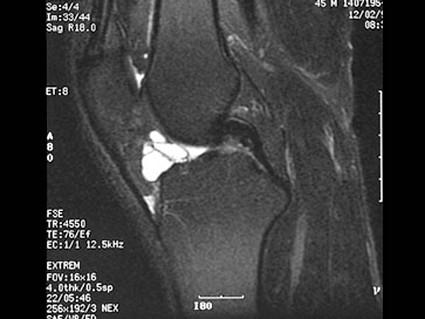

问题 男,45岁,右膝关节曾有外伤史,右膝关节活动后感不适数月,请结合所提供的图像,选择最佳选项 ( )

选项 A、半月板损伤 B、后十字韧带撕裂 C、前十字韧带撕裂 D、前十字韧带腱鞘囊肿 E、未见异常

答案 D